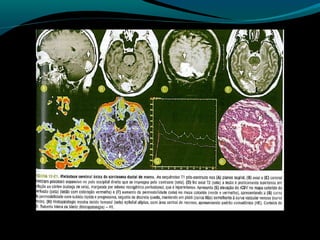

Astrocitoma difuso (GRAU II OMS)

Bem diferenciado;

Grau II;

10 a 15% dos astrocitomas;

Entre 20 a 45 anos;

Crescimento lento;

Tendência para degeneração maligna;

2/3 supratentoriais (frontal e temporal);

Convulsão e cefaléia;

Grau II, tendência à progressão para astrocitoma

anaplásico;

TC:

lesão hipo ou isodensa;

Geralmente NÃO se impregna por contraste ( se sim,

pensar em degeneração maligna);

RM:

Aspecto aparentemente circunscrito mas tumor se

infiltra;

Hipointenso em T1 e hiper em T2 e FLAIR;

Realce pelo Gd no tumor ou leptomeninge  pensar em

degeneração maligna;

Discreta redução do NAA;

Aumento do Co;

Aumento da relação Mi/Cr;

Valores do coeficiente de difusão aparente aumentados;

Baixa perfusão;

Recomendações:

RM associada às técnicas (ERM, difusão, perfusão)

método de escolha para detecção, controle evolutivo,

e controle pós-operatório;

Astrocitoma anaplásico

Tumor com anaplasia focal ou difusa de origem

astrocítica classificado como grau III pela OMS;

33% dos astrocitomas;

Clínica variada;

Pacientes acompanhados com grau II que apresentam

deterioração clínica  III

Origem;

Tendência a progressão para astrocitoma grau IV

(glioblastoma  proliferação vascular e necrose);

Imagem:

Lesão infiltrativa com limites indefinidos;

É esperado infiltração do tumor na substância branca

adjacente;

Heterogeneidade de sinal é maior que no grau II, mas

predomina hipo em T1 e Hiper em T2 e FLAIR;

Imagem:

Após Gd: regiões de quebra da BHE;